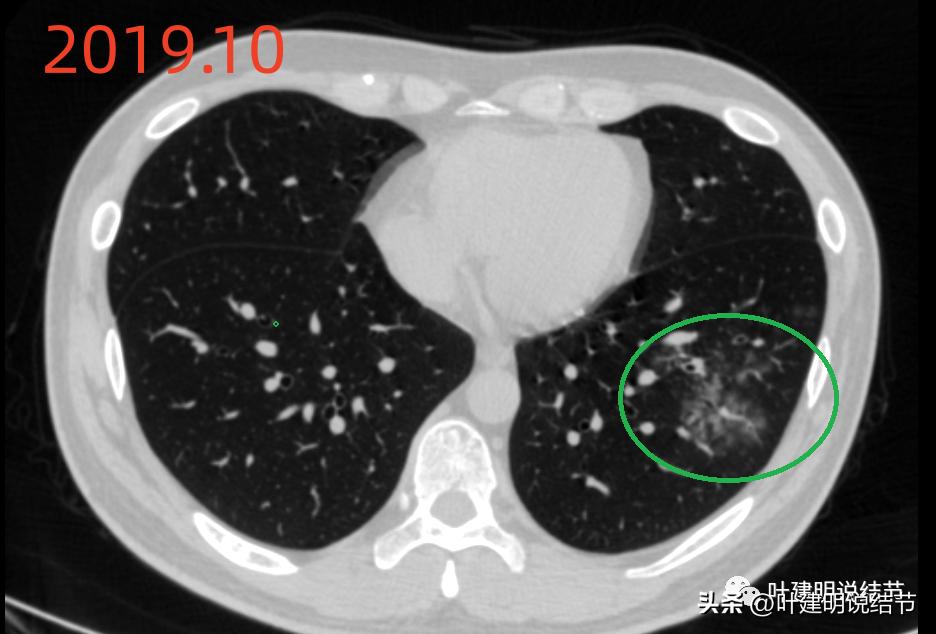

当时左下有肺炎。

上图是不是病灶A所在的地方?旁边 还有其他两处磨玻璃密度的结节。

上图也是当时左下的炎性区域。